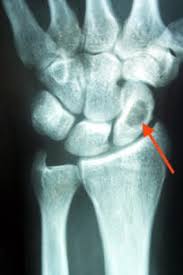

1 2 3 4 5 6. Hier ist die Radiusfraktur nicht mit einer Platte sondern mit Kirschnerdrähten erfolgt. Wenn nun diese Schrauben entfernt werden kann es passieren dass die Knochen dann keinen Halt mehr haben und auseinander oder zusammen fallen.

Gelegentlich ist es nicht möglich das Material vollständig zu entfernen so dass es auch vorkommen kann dass Reste des Metalls im Körper belassen werden müssen. Ich habe neulich das Gleiche bei einem Schrank erlebt. Die Stabilität sollte nach der Entfernung kein Problem sein weil die Schrauben und Nägel immer versetzt angeordet sind also die Löcher nie über- untereinander lägen. Die ist hart und sehr spitz und lässt sich nicht bewegen. Sollten Metallteile weggebrochen sein werden die dann auch im Knochen belassen die tun nix. Hier ist die Radiusfraktur nicht mit einer Platte sondern mit Kirschnerdrähten erfolgt. Obwohl ein Schraubenloch noch lange im Röntgenbild nachweisbar ist kommt es zu einer fortschreitenden Geflechtknochenbildung die die Stresskonzentration im Schraubenloch zunehmend herabsetzt. Hierbei wird in manchen Fällen lediglich die einzelne Stellschraube entfernt wobei die komplette Metallentfernung ungefähr nach einem Jahr beginnt. Auch nach einem Jahr kann man im Röntgenbild nach einer Schraubenentfernung die Schraubenkanäle gut erkennen.